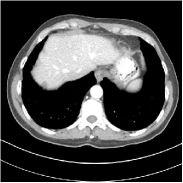

Fig. 3 illustrates the image evolution over SUPER layers (i.e., with evolving network weights in the iterative reconstruction process) for one test case, when using SUPER-WRN-ULTRA. It is apparent that in the early SUPER layers, the proposed SUPER-WRN-ULTRA method mainly removes noise and artifacts, while later SUPER layers mainly reconstruct details such as the bone structures shown in the zoom-in box. A similar behaviour is observed with FBPConvNet-based SUPER methods, which are shown in the supplement (Figs. 13 and 14).

Refer to caption Refer to caption Layer 1RMSE =27.44 HURefer to caption Refer to caption Layer 5RMSE = 26.03 HU

Refer to caption Refer to caption Layer 11RMSE = 25.91HURefer to caption Refer to caption Reference

Figure 3: Image evolution over SUPER layers using the SUPER-WRN-ULTRA method. RMSE values are also indicated.